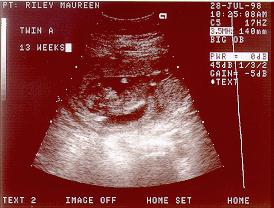

July 28, 1998

12 Weeks, 5 days

Twin "A"

Similarly, "Abigail" had to duplicate the pose, just to make it hard to tell them apart, and showed a right profile. Looking a lot more like a little baby now, and as indicated above, a lot of activity.

It is quite easy when they are doing the ultra sound to see the outline of the arms, legs, toes, and even the membrane surrounding the fetus.

But I have to admit, that I'm not getting much better at reading the ultra sounds.